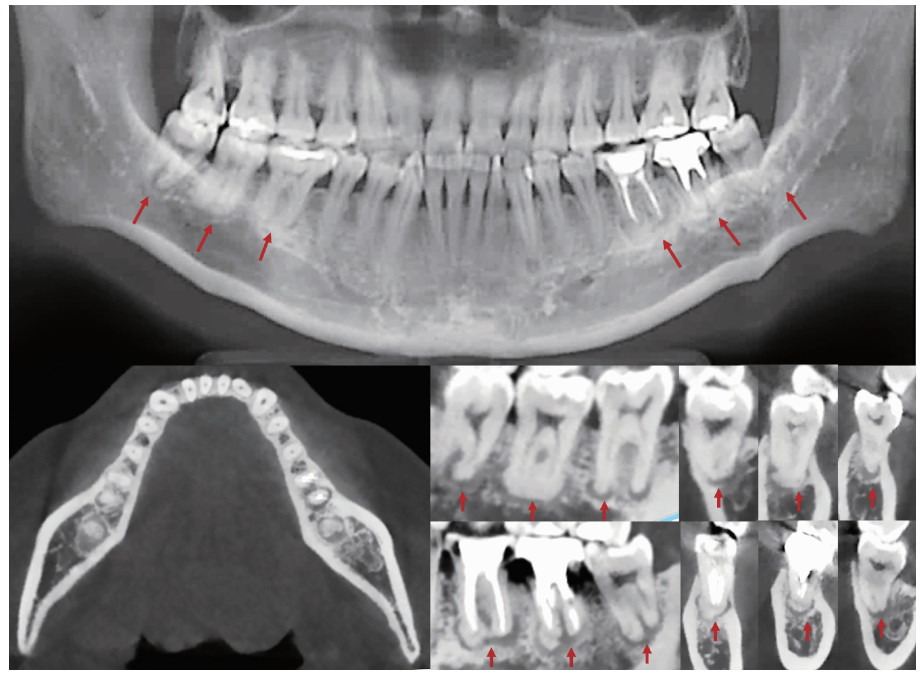

Figure 3

Intraoral images at 1-year follow-up"